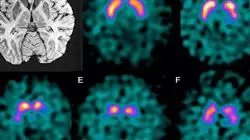

Embora a publicidade e o marketing insistam constantemente que a velhice pode ser evitada, a verdade é que isso não é correto, embora possa ser adiada. Trata-se de um processo biológico que afeta toda a sociedade e embora existam inúmeros tratamentos para aliviar suas consequências, mais cedo ou mais tarde eles acabam tendo um impacto considerável sobre a saúde física e cognitiva da pessoa. É precisamente sobre as mudanças que ocorrem durante este processo que a Gerontologia se concentra, que determinou as causas do Estresse Oxidativo que leva à deterioração da membrana celular e, portanto, ao envelhecimento acelerado.